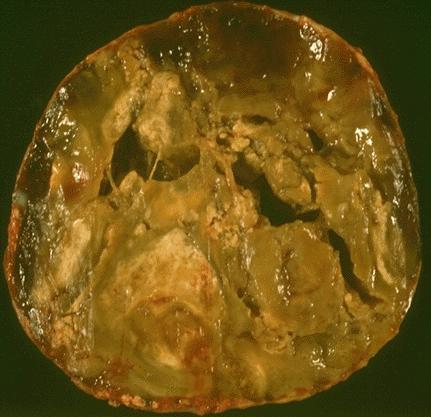

Gross description

- Solitary, encapsulated nodule; multiple if familial

- Variable size (1 - 10 cm)

- Solid, gray-white, tan to light brown

- Secondary changes: hemorrhage, cystic change, fibrosis, calcification, infarction; may develop post-fine needle aspiration cytology

- Rarely black; especially seen with minocycline therapy

Gross images

Contributed by Andrey Bychkov, M.D., Ph.D., Mark R. Wick, M.D. and AFIP

Images hosted on other servers: